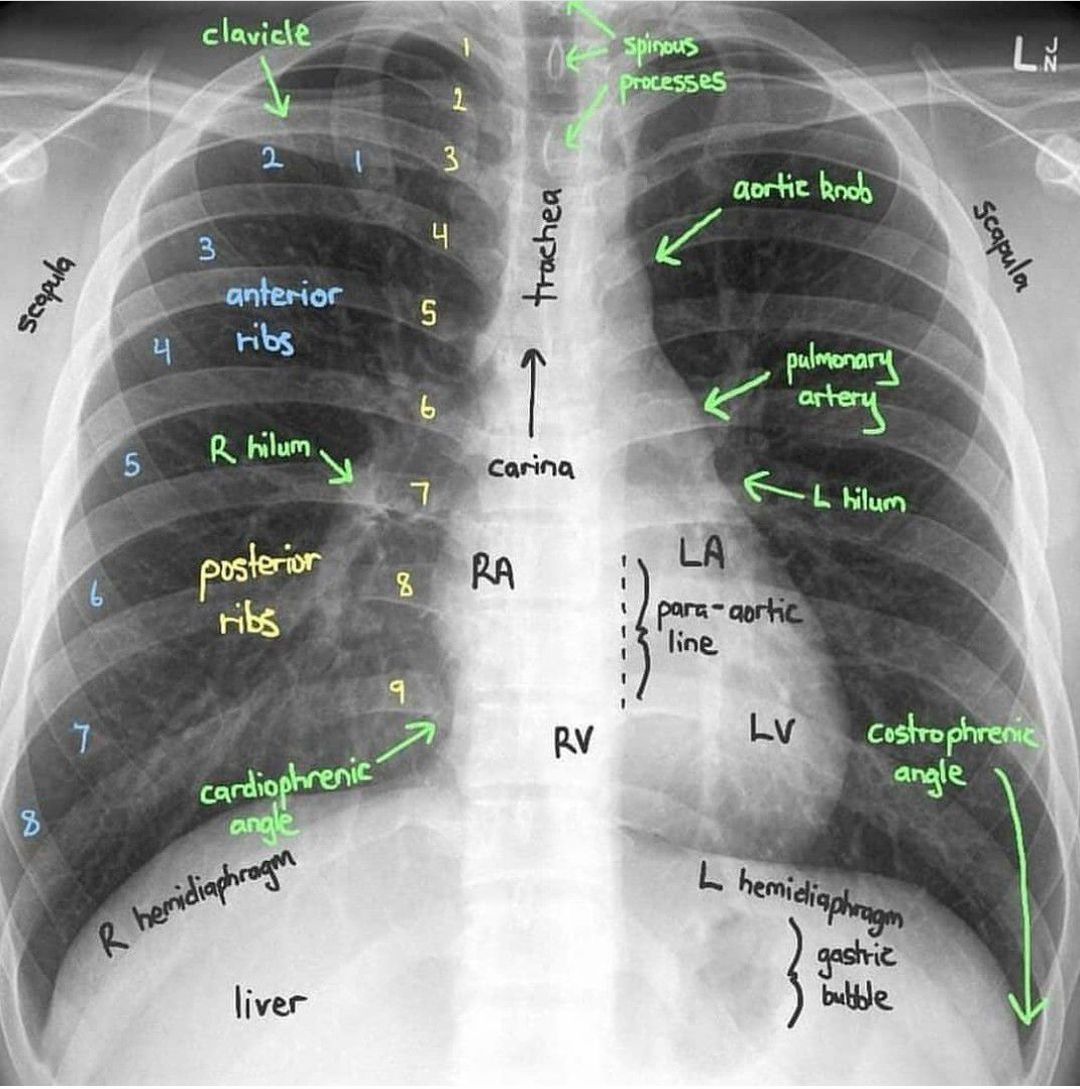

Chest radiograph (CXR)

Medicine

Health

Cxr